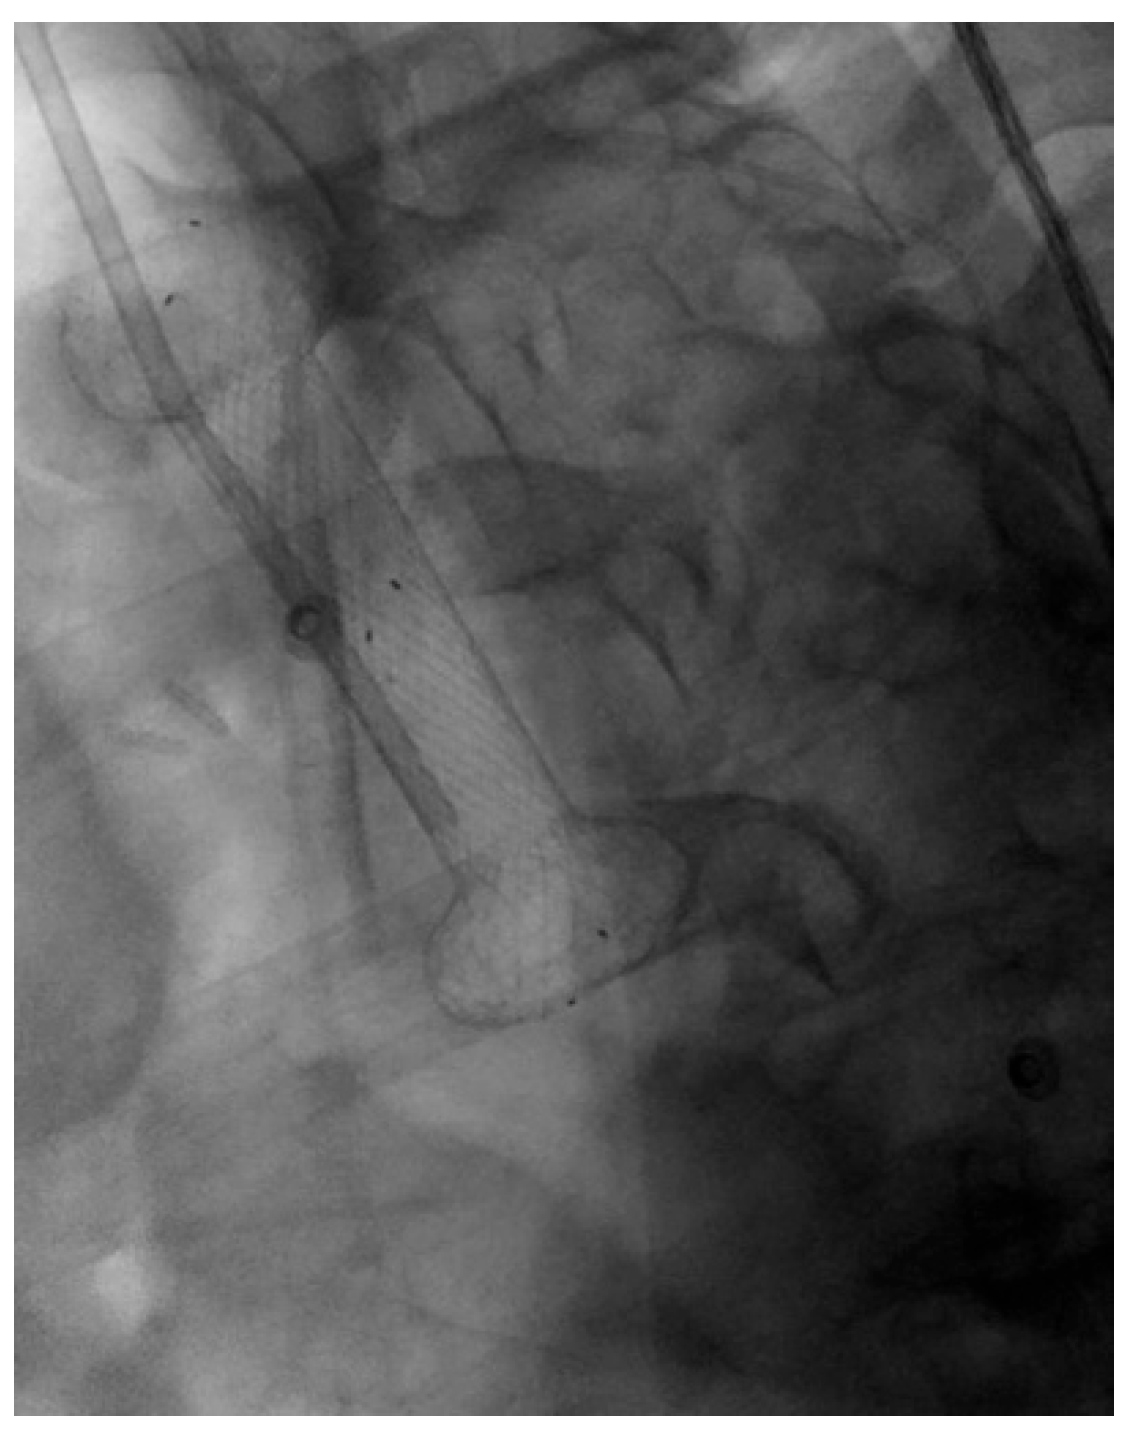

4.1.2. LAMS

Indication and Mechanism of Action

- Direct technique: puncture of the jejunal loop with a 19G needle and contrast injection to confirm position [126].

- Device-assisted EUS-GE: balloon or enteroscope passed across the stenosis to aid EUS visualization and targeting [127].

- Wireless Endoscopic Simplified Technique (WEST): described by Bronswijk et al. in 2020 and currently the most widely used technique [128], this approach involves jejunal distension via a nasoenteric tube with saline and dye, followed by “free-hand” single-step LAMS deployment under EUS guidance [128].

Efficacy and Adverse Events

- Type 1 (63.1%): distal flange in the peritoneum, proximal in the stomach, without enterotomy—managed with LAMS removal and OTSC placement.

- Type 2 (30.4%): distal flange in the peritoneum, proximal in the stomach, with confirmed enterotomy—managed with repeat LAMS or LAMS-in-LAMS bridging.

- Type 3 (2.2%): distal flange in the small bowel, proximal in the peritoneum—managed surgically.

- Type 4 (4.3%): distal flange in the colon, proximal in the stomach—managed conservatively or surgically after tract maturation.